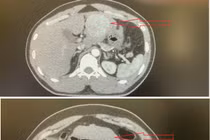

Người bệnh từng có u gan đã được đốt và nút mạch nhưng do xơ gan đã xuất hiện thêm khối u mới tiến triển nhanh, dẫn đến vỡ và chảy máu.

Tỷ lệ tử vong sau mổ cấp cứu trong vỡ u gan nặng có thể lên đến 70-80%. Đặc biệt, bệnh nhân sốc mất máu do vỡ u gan trên nền u gan đa ổ, viêm gan B.

Nhiều người bệnh không biết bản thân bị ung thư gan cho đến khi khối u vỡ, gây xuất huyết trong ổ bụng, nguy hiểm tính mạng.